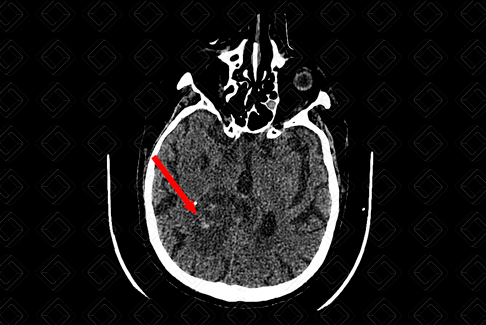

Texto alternativo para a imagem Figura 1. Créditos: Dra. Elazir Mota - Rio de Janeiro/RJ

Descrição das figuras 1 e 2: Tomografia computadorizada do crânio, estudo sem contraste (paciente com injúria renal aguda), planos axial e sagital, evidenciando lesão infiltrativa, de limites mal definidos, heterogênea, com áreas de sangramento, na substância branca profunda do lobo parietal direito (setas vermelhas). O histopatológico revelou que trata-se de glioblastoma.

• Tomografia computadorizada do crânio com contraste venoso: Tumor mais frequentemente na região supratentorial, com preferência pelos lobos frontal e parietal, infiltrando a substância branca. Trata-se de lesão expansiva, em geral, volumosa no momento do diagnóstico, hipodensa ou isodensa, de limites mal definidos e necrose central. Em 95% dos casos, apresentam ávida captação pelo contraste venoso (realce pode ser heterogêneo, irregular ou anelar) (f iguras acima);